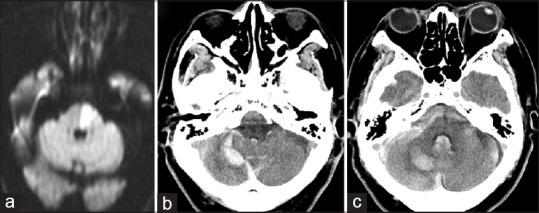

A 75-year-old man experienced sudden disturbance of consciousness; computed tomography demonstrated cerebellar and subarachnoid hemorrhage due to a ruptured distal PICA aneurysm. Neck clipping of the aneurysm prevented re-rupture initially, and superficial temporal artery-superior cerebellar artery (STA-SCA) bypass was performed 3 months after admission. Postoperative angiography confirmed patency of the bypass, and the patient was discharged without any new neurological deficits.

This report describes a case of development of a saccular distal PICA aneurysm after atherosclerotic basilar artery occlusion. We believe that increased hemodynamic stress at the PICA might have contributed to the occurrence and rupture of the aneurysm. STA-SCA bypass, introduced in the territory of the cerebellar hemisphere, reduces hemodynamic stress, which would prevent the occurrence of aneurysm and recurrent bleeding.